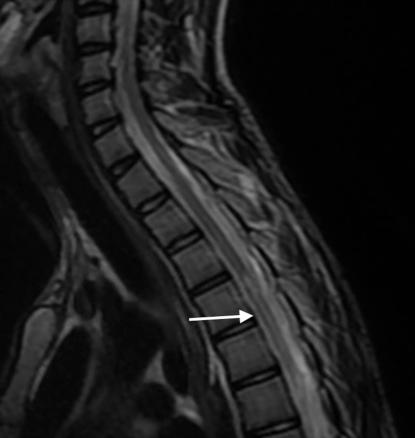

Une IRM médullaire est réalisée en urgence, mettant en évidence une anomalie de signal centromédullaire étendue de T4 à T6 en hypersignal T2 – réalisant un aspect en « œil de hibou » –, avec une restriction en diffusion et sans prise de contraste après injection de gadolinium (fig. 1).

Le diagnostic d’ischémie médullaire reste difficile à poser avec une IRM à l’aspect souvent normal de la moelle épinière sur les séquences T1 et T2. Si le tableau clinique évoque la possibilité d’une ischémie, les séquences de diffusion doivent compléter le bilan IRM. Les résultats de l’IRM de diffusion demeurent cependant aléatoires en raison d’une qualité d’image souvent insuffisante. Le contrôle IRM réalisé après vingt-quatre à quarante-huit heures confirme le diagnostic en visualisant un signal hyperintense en T2 de topographie centromédullaire de part et d’autre de la ligne médiane, correspondant au territoire de l’artère spinale antérieure (image en « œil de serpent » ou en « œil de hibou »). Au-delà de quarante-huit heures, l’IRM peut visualiser un effet de masse, et une prise de contraste est souvent observée. À la phase séquellaire, il est classique de noter une atrophie médullaire avec de petites cavitations intramédullaires de part et d’autre de la ligne médiane.1